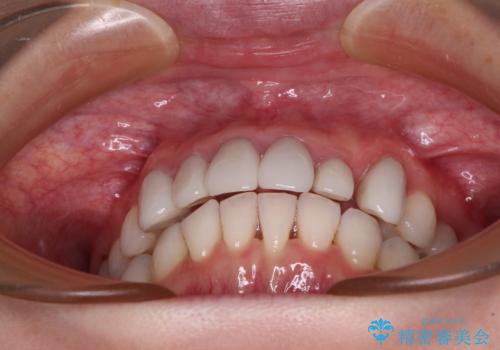

- 全体的なデコボコと、奥歯の欠損を放置した結果倒れ込んだ奥歯などを気にして来院された患者様です。

ワイヤー矯正の方が理想的な仕上がりとできる状態でしたが、上顎前歯にクラウンが装着されているため、インビザラインにて矯正治療を行うこととしました。

インビザラインのみで対応できないときにはワイヤー矯正を併用することとし、矯正治療後にはオールセラミッククラウンによる補綴治療を行うこととしました。

矯正治療自体はインビザラインで満足のいく仕上がりとなりました。

前歯は根管治療が必要となり、元々舌側に入り込んでいた左上2番目の歯は歯周外科処置により歯肉ラインを整えることとしました。

欠損部位は傾斜歯軸を起き上がらせることができたため、オールセラミッククブリッジにて補綴治療を行いました。

全顎的に満足のいく仕上がりとなりました。